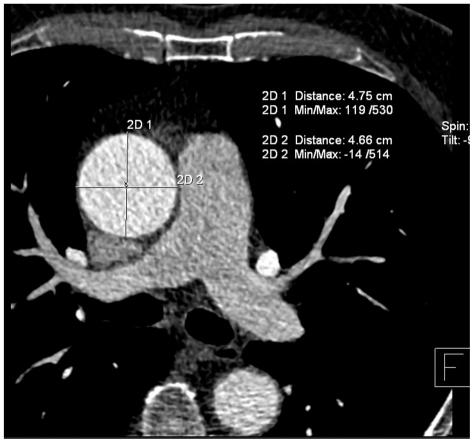

To evaluate the spectrum, prevalence, and significance of incidental non-cardiac findings (INCF) in patients referred for a non-invasive coronary angiography using a 128-slice multi-detector CT (MDCT).

The study subjects included 1,044 patients; 774 males (mean age, 59.9 years) and 270 females (mean age, 63 years), referred for a coronary CT angiography on a 128-slice MDCT scanner. The scans were acquired from the level of the carina to just below the diaphragm. To evaluate INCFs, images were reconstructed with a large field of view (> 300 mm) covering the entire thorax. Images were reviewed in the axial, coronal, and sagittal planes, using the mediastinal, lung, and bone windows. The INCFs were classified as severe, indeterminate, and mild, based on their clinical importance, and as thoracic or abdominal based on their locations.

Incidental non-cardiac findings were detected in 56% of patients (588 of 1,044), including 435 males (mean age, 65.6 years) and 153 females (mean age, 67.9 years). A total of 729 INCFs were observed: 459 (63%) mild (58% thoracic, 43% abdominal), 96 (13%) indeterminate (95% thoracic, 5% abdominal), and 174 (24%) severe (87% thoracic, 13% abdominal). The prevalence of severe INCFs was 15%. Two severe INCFs were histologically verified as lung cancers.

The 128-slice MDCT coronary angiography, in addition to cardiac imaging, can provide important information on the pathology of the chest and upper abdomen. The presence of severe INCFs is not rare, especially in the thorax. Therefore, all organs in the scan should be thoroughly evaluated in daily clinical practice.

评估使用 128 层多探测器 CT(MDCT)进行非侵入性冠状动脉造影检查的患者中偶然的非心脏发现(INCF)的谱、患病率和意义。

研究对象包括 1044 名患者;774 名男性(平均年龄 59.9 岁)和 270 名女性(平均年龄 63 岁),因冠状动脉 CT 血管造影而在 128 层 MDCT 扫描仪上接受检查。扫描范围从隆突到膈肌以下。为了评估 INCF,使用大视野(>300mm)重建图像,覆盖整个胸部。在轴位、冠状位和矢状位平面上,使用纵隔、肺和骨窗对图像进行了评估。根据其临床重要性,将 INCF 分为严重、不确定和轻度,并根据其位置分为胸部或腹部。

在 56%的患者(1044 名患者中的 588 名)中发现了偶然的非心脏发现,包括 435 名男性(平均年龄 65.6 岁)和 153 名女性(平均年龄 67.9 岁)。共观察到 729 例 INCF:459 例(63%)轻度(58%胸部,43%腹部),96 例(13%)不确定(95%胸部,5%腹部)和 174 例(24%)严重(87%胸部,13%腹部)。严重 INCF 的患病率为 15%。2 例严重 INCF 经组织学证实为肺癌。

128 层 MDCT 冠状动脉造影术除了心脏成像外,还可以提供有关胸部和上腹部病理学的重要信息。严重 INCF 的存在并不罕见,尤其是在胸部。因此,在日常临床实践中,应彻底评估扫描中的所有器官。